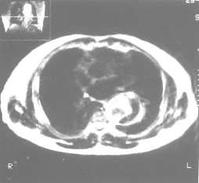

胸部平片見上縱隔或主動脈弓影增大,主動脈外形不規則,有局部隆起。如見主動脈內膜鈣化影,可準確測量主動脈壁的厚度。正常在2mm~3mm,增到10mm時則提示夾層分離可能性,若超過10mm則可肯定為本病。主動脈造影可以顯示裂口的部位,明確分支和主動脈瓣受累情況,估測主動脈瓣關閉不全的嚴重程度。缺點是它屬於有創性檢查,術中有一定危險性。CT可顯示病變的主動脈擴張。發現主動脈內膜鈣化優於X線平片,如果鈣化內膜向中央移位則提示主動脈夾層,如向外圍移位提示單純主動脈瘤。此外CT還可顯示由於主動脈內膜撕裂所致內膜瓣,此瓣將主動脈夾層分為真腔和假腔。CT對降主動脈夾層分離準確性高,主動脈升、弓段由於動脈扭曲,可產生假陽性或假陰性。但CT對確定裂口部位及主動脈分支血管的情況有困難,且不能估測主動脈瓣關閉不全的存在。